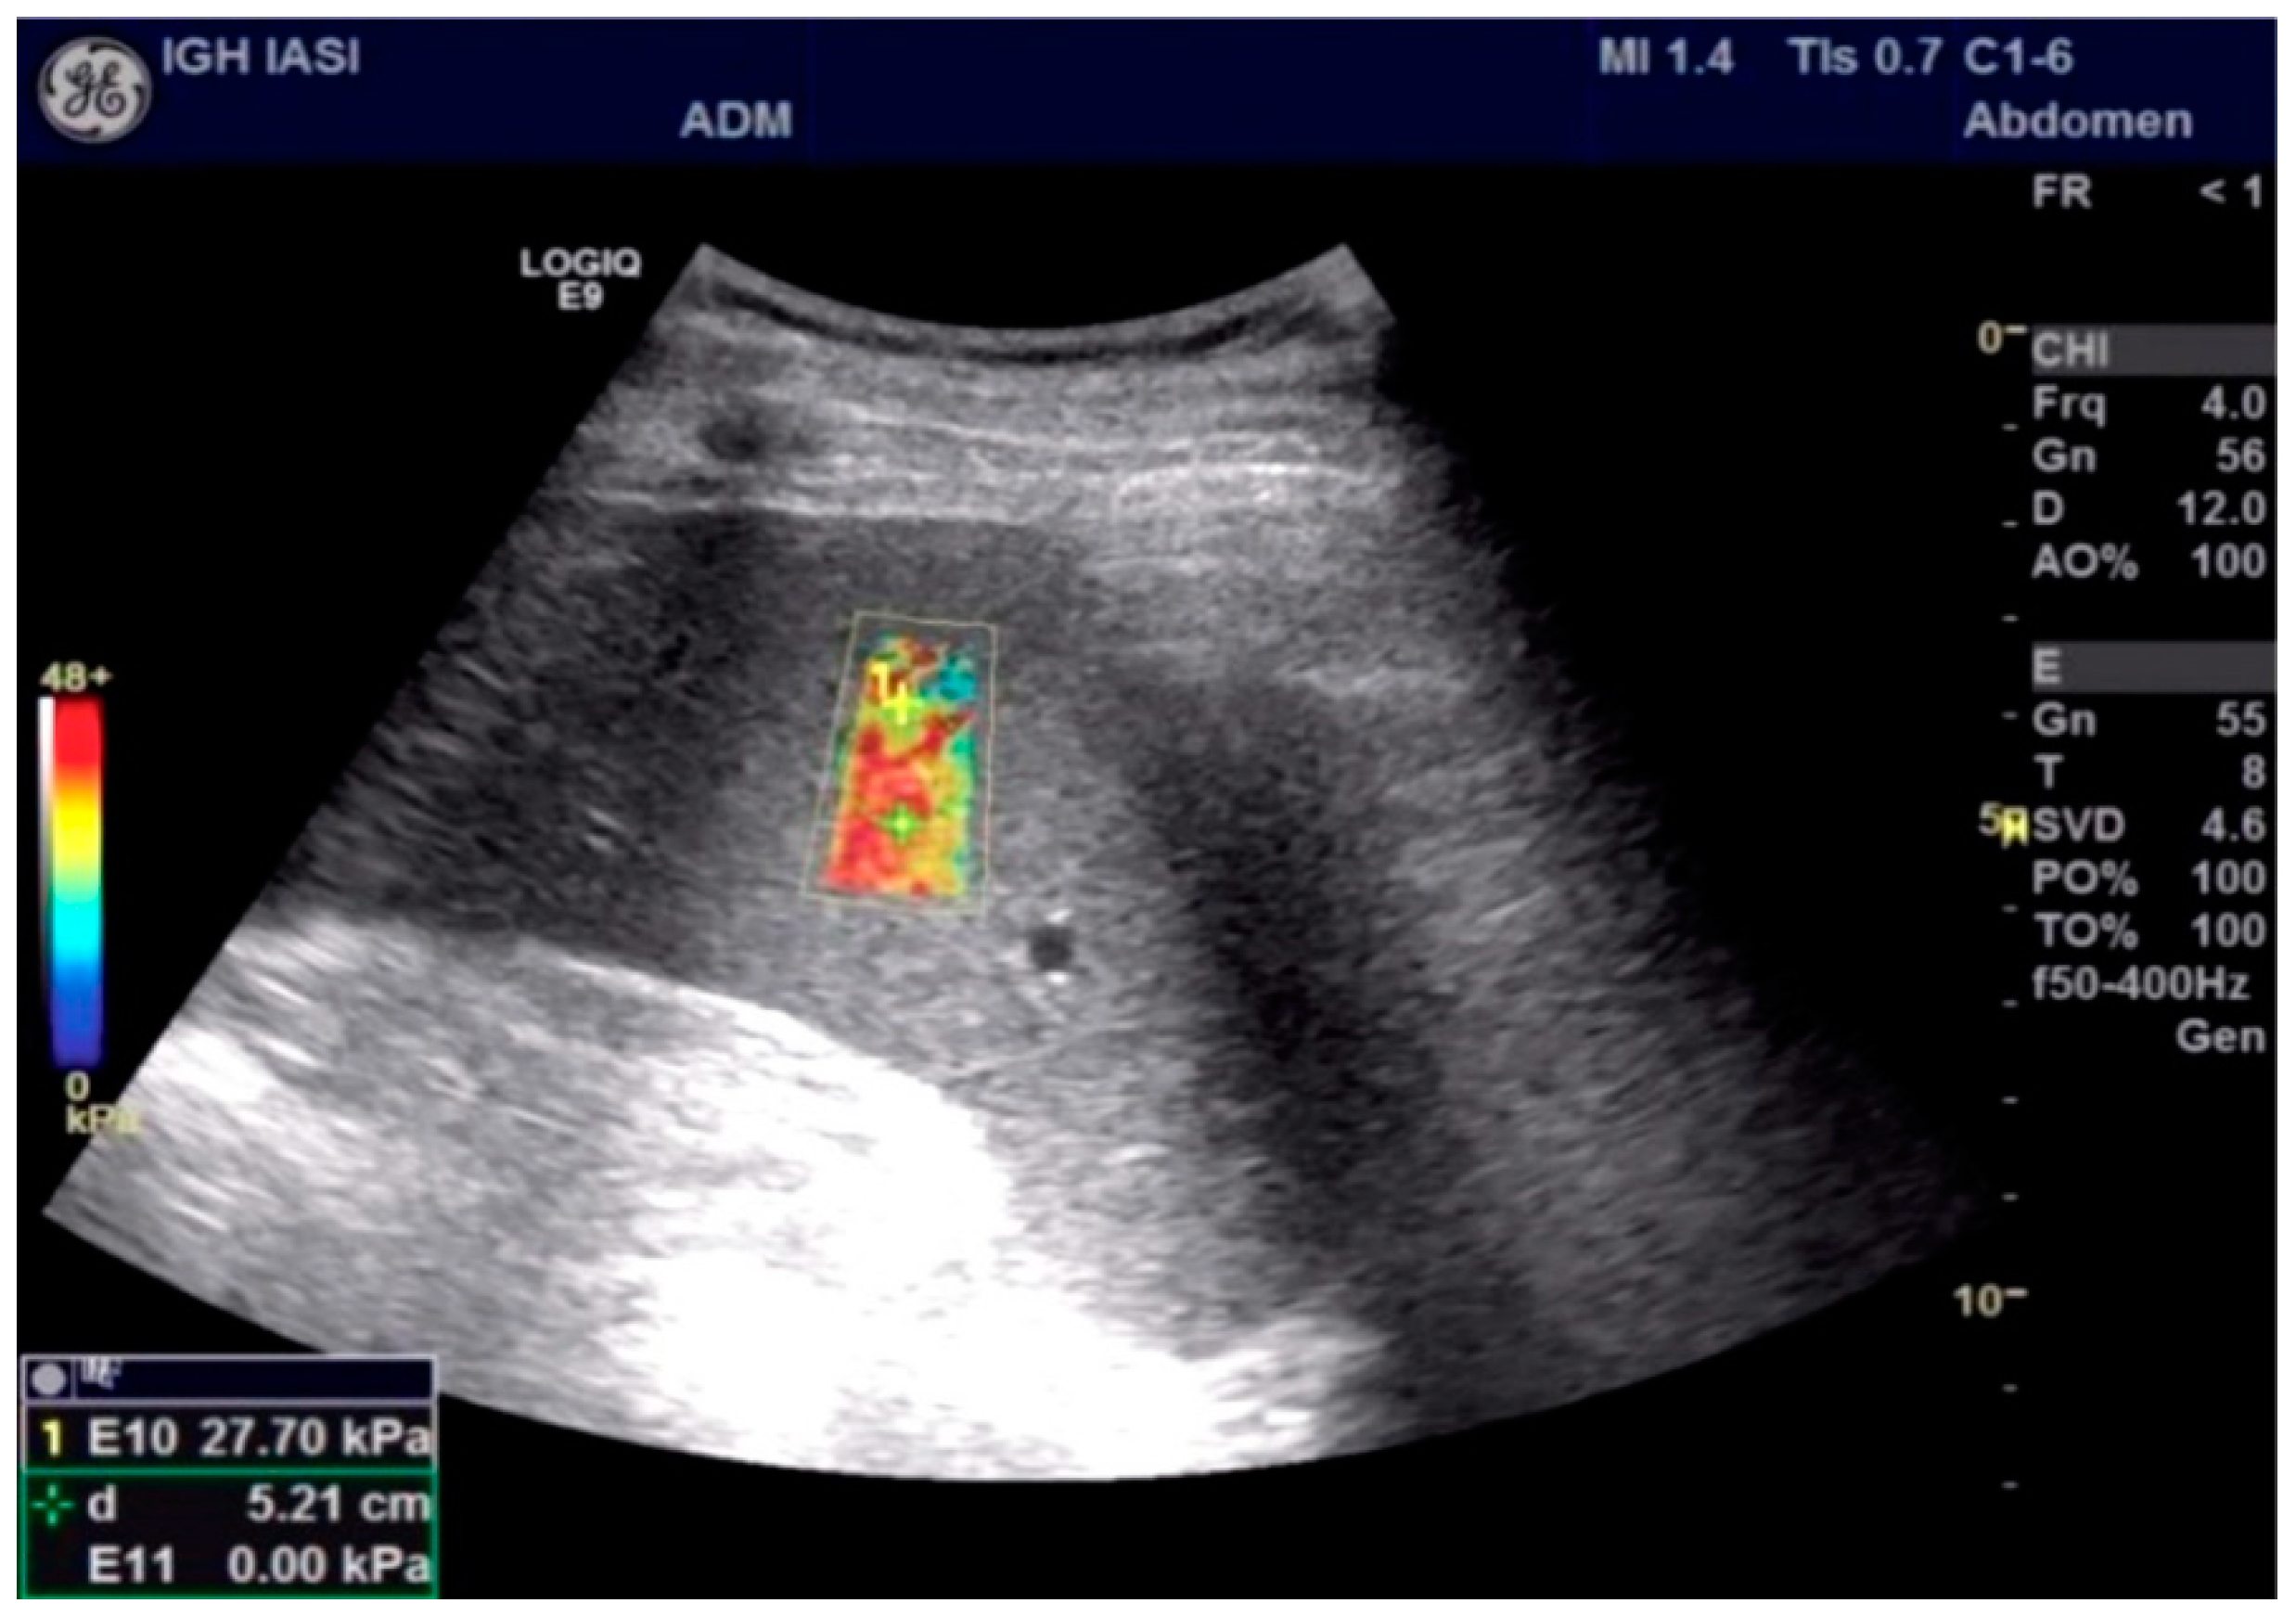

| SS (kPa) | 17.67 ± 4.48 | 22.20 ± 3.98 | 14.94 ± 1.67 | <0.001 |

| SS | 0.987 | 0.964 ÷ 1.000 | 0.000 | 17.95 | 94.40% | 96.70% |